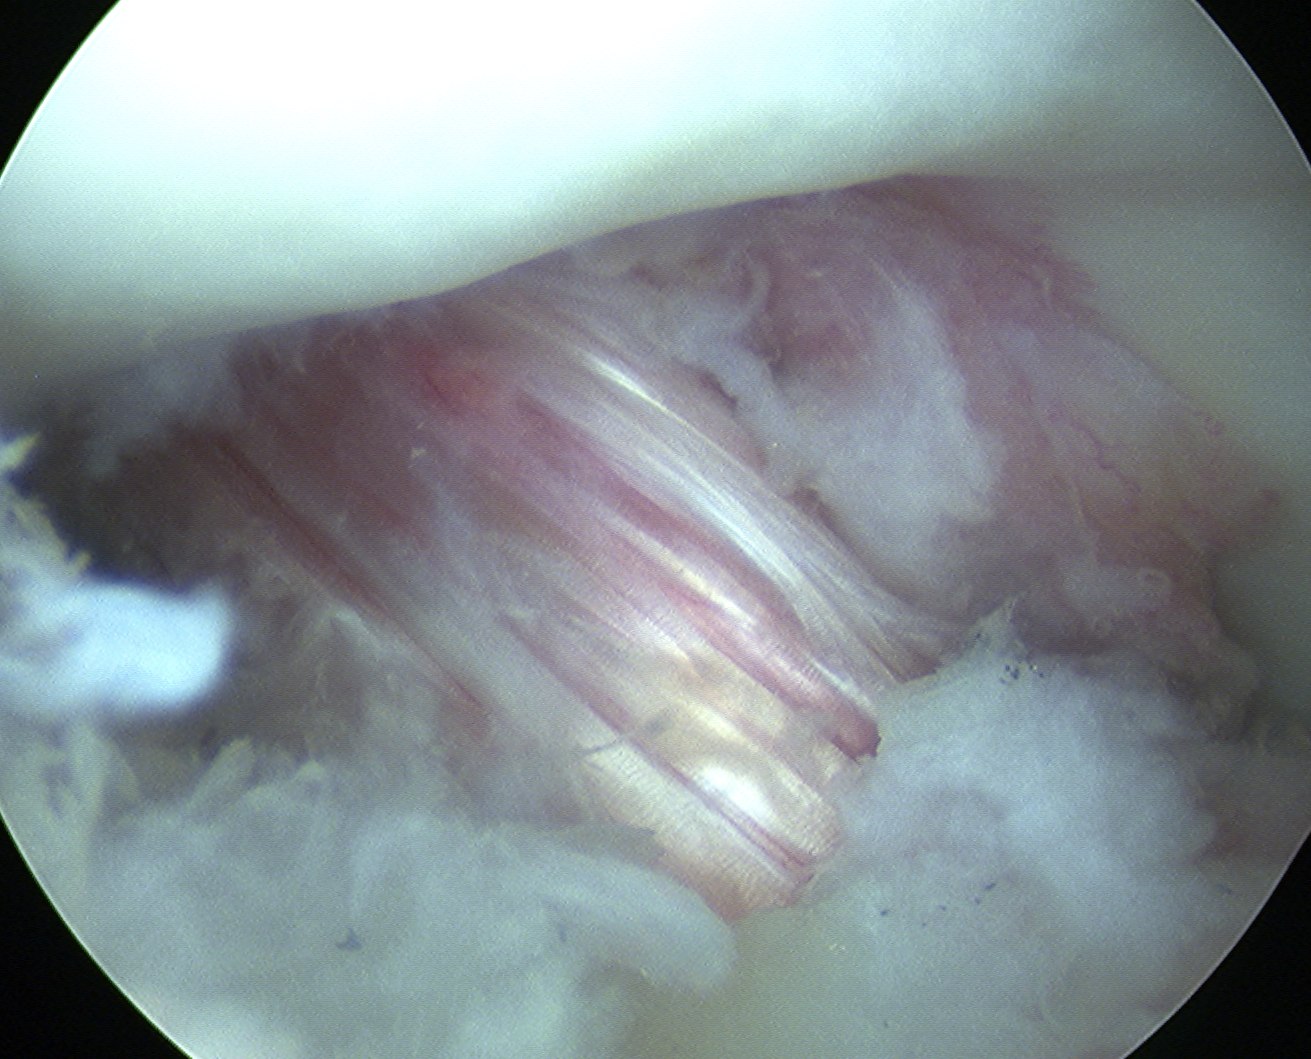

Pass graft

- ensure bone plug passes easily into tibial tunnel

- pull up gently on sutures and advance the bone plug into knee

- use grasper to align the bone plug with the femoral tunnel

- then pull on sutures and advance the plug into the tennel

- pull femoral bone plug deep into tunnel and tension